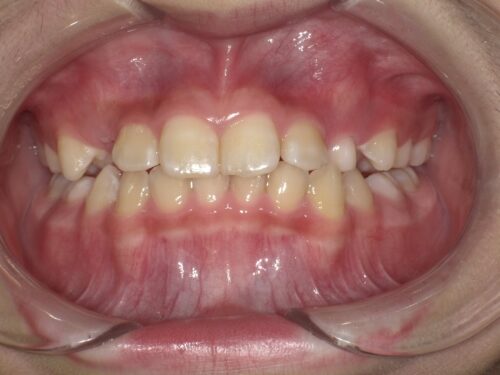

今回は前歯の歯並び、噛み合わせが気になると来院された患者さんです。

初診時の口腔内写真です。

前歯の噛み合わせが逆になっているのが分かると思います。

上の真ん中の前歯2本と下の前歯4本は永久歯です。

また、真ん中から向かって左に2本目は乳歯ですが、これも反対の噛み合わせになっています。

今の状態は歯の生える向きの問題、上顎の前方への成長不良によるものと考えます。

この状態のまま放置しておくと、下の前歯が上の前歯に押されるため下顎が前方に成長していってしまいます。

それにより骨格的な問題が出てしまう可能性があります。

そのため早めの改善を目指し、矯正治療をおすすめしました。